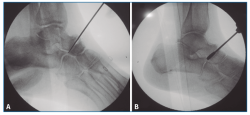

Figura 1. Cruentación de la articulación astrágalo-escafoidea, bajo control fluoroscópico, hasta tejido subcondral, con escoplos (A) y brocas motorizadas (B).

En primer lugar, se aborda la articulación TN como indican Carranza et al.(29); para ello, se marca en la piel el paquete neurovascular dorsal, se chequea la articulación por control fluoroscópico con una aguja intramuscular colocada entre el tendón tibial anterior (TA) y el extensor largo (EHL). Se realiza una incisión solo cutánea de 1 cm sobre la línea articular como el portal artroscópico dorsomedial descrito por Lui(24). Para evitar lesionar la arteria pedia o el nervio peroneal profundo, se realiza disección roma y penetración de la articulación astrágalo-escafoidea lo más cerca posible del TA. Finalmente, se cruenta la articulación bajo control fluoroscópico hasta tejido subcondral con escoplos y brocas motorizadas (Figura 1).